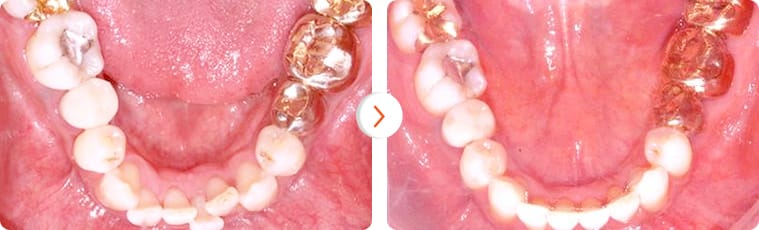

“Khách hàng nam 30 tuổi chỉnh hình răng sử dụng minivis sau 15 tháng”

Trường hợp lệch khớp cắn nhẹ. Bệnh nhân nữ 25 tuổi – Thời gian điều trị: 8 tháng